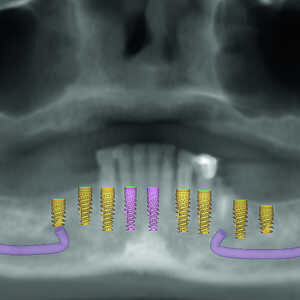

La patiente est revenue pour passer la visite des enregistrements. Au cours de celle-ci, des empreintes maxillaires et mandibulaires ont été prises afin de fabriquer des prothèses provisoires immédiates qui seraient mises en place lors de la visite prévue pour la chirurgie. Le scanner CS 8100 3D (Carestream Dental) a été utilisé pour acquérir des images CBCT, et obtenir ainsi les données nécessaires au plan de traitement virtuel. Les données 3D acquises grâce à la numérisation CBCT ont permis de déterminer les paramètres idéaux de longueur, de largeur et de positionnement des implants, aux endroits clés des arcades édentées de la patiente, soit les régions des premières molaires, premières prémolaires, canines et incisives centrales (Figs. 3–6). Des guides chirurgicaux à appui osseux maxillaire et mandibulaire ont été produits d’après le plan de traitement numérique conçu par 3D Diagnostix (Figs. 7 et 8).

Fig-3-Présentation-du-traitement-de-l’arcade-maxillaire-300x300-

Fig-4-Présentation-du-traitement-de-l’arcade-mandibulaire-300x300-

Fig-5-Analyse-dento-faciale-du-traitement-implantaire-proposé-dans-l’arcade-maxillaire-300x300-

Fig-6-Analyse-dento-faciale-du-traitement-implantaire-proposé-dans-l’arcade-mandibulaire-300x300-